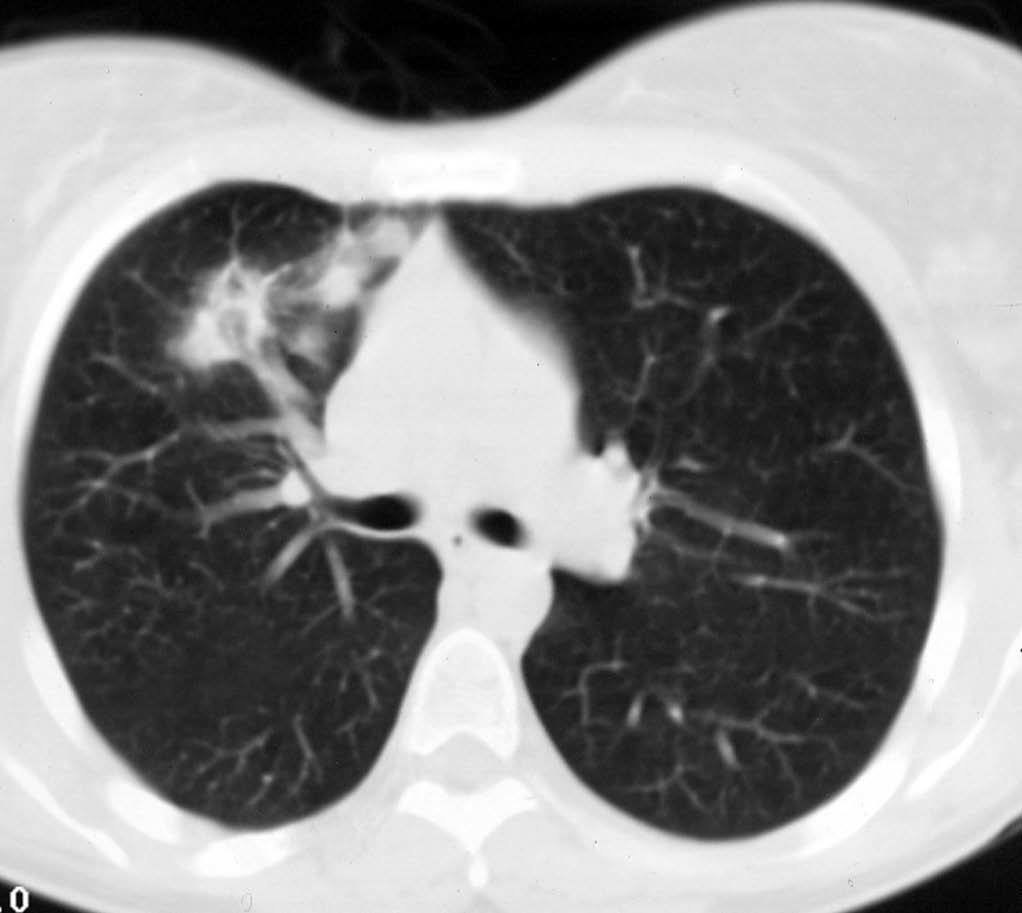

Mujer de 26 años de edad, fumadora de 10 cigarrillos al día, sin otros antecedentes de interés, que consulta por dolor torácico pleurítico sin fiebre, ni otra sintomatología acompañante. Las pruebas de laboratorio fueron normales. En la radiografía de tórax se observó una lesión redondeada de unos 3 cm en el lóbulo superior derecho, parahiliar (fig. 1). Ante la posibilidad de que se tratara de una neumonía redonda, recibió tratamiento antibiótico empírico con amoxicilina-clavulánico, sin cambios radiológicos. Se realizó una tomografía computarizada (TC) torácica sin contraste intravenoso, que mostró un nódulo pulmonar de bordes mal delimitados de 2 x 3 cm en el segmento anterior del lóbulo superior derecho, con tres nódulos satélites adyacentes (figs. 2 y 3). La fibrobroncoscopia fue normal. La citología del broncoaspirado y cepillado bronquial fue negativa para malignidad. Los cultivos para bacterias, hongos y micobacterias resultaron estériles. Se practicó una punción aspiración con aguja fina (PAAF) transtorácica bajo control con TC, obteniéndose material sin evidencia de malignidad. Ante la ausencia de diagnóstico y la imposibilidad para descartar malignidad se realizó una lobectomía superior derecha.

Fig. 2.--Tomografía computarizada helicoidal sin contraste, con cortes de 8 mm a la altura de ventana aortopulmonar, muestra un nódulo sólido de márgenes mal definidos, en segmento anterior de lóbulo superior derecho.